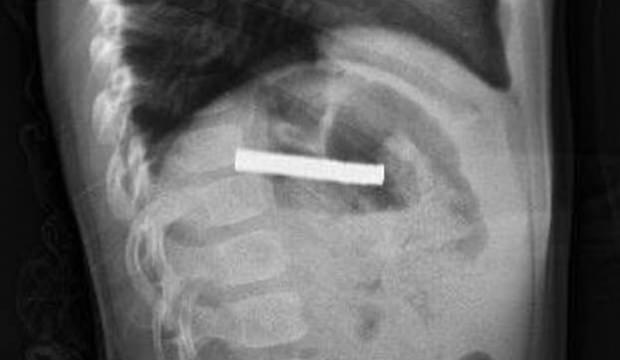

Fırat Üniversitesi Çocuk Gastroenteroloji Hepatoloji ve Beslenme Bilim Dalı Başkanı Prof. Dr. Yaşar Doğan, çocuk hastanın yemek borusuna yapışmış 19 mıknatısı endoskopik yöntemle çıkardı.

Mıknatıslar uzun süre yemek borusunda takılı kaldığı için yemek borusu ve mide girişinde zedelenmeler olurken, çocuğun sağlık durumunun iyi olduğu ve taburcu edildiği öğrenildi.